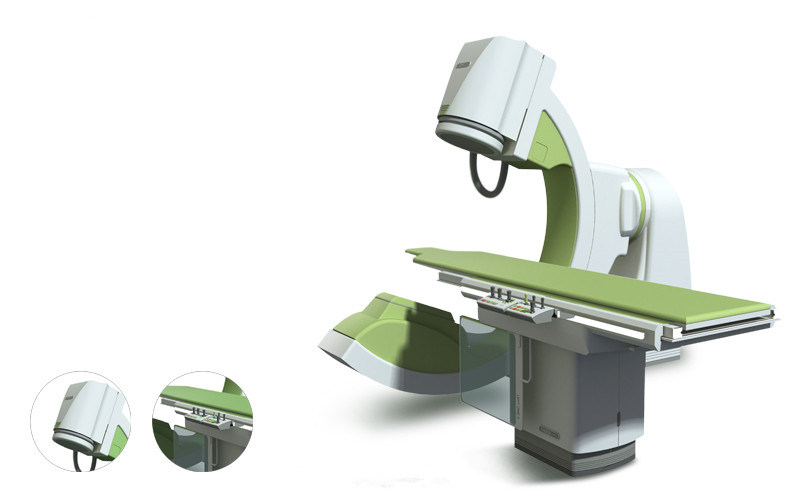

案例展示 ∥ 影像类设备 ∥ 系列放射类设备

2007年,设计团队花了近一年的时间来完成从机构到风格设计、工业设计、产品制造等全部工作。包括细节上的扶手、玻璃罩的设计,使外观更加富有设计感,但并非夸张复杂的设计风格,主要以功能为主,在满足产品功能的基础上,再进行了形式上的优化与风格的统一,我们经过与客户的紧密合作,出色地完成了客户的项目。

客户 | TCL医疗

项目 | 系列放射类设备

年份 | 2006